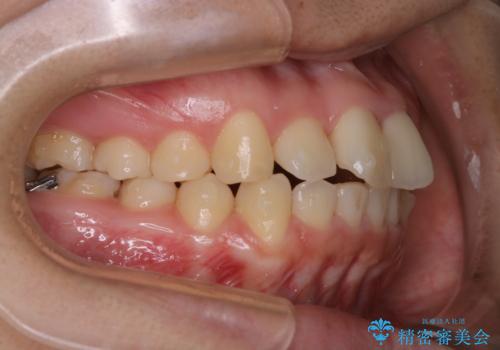

- 前歯が捻転していることを主訴に来院された方です。元々は部分矯正をご希望されていましたが、噛み合わせ等総合的に治療していくためインビザラインにて全顎的に治療を行うこととしました。

元々は上の前歯部の捻転のみの治療をご希望されていましたが、下の前歯もがたつきがあることや噛み合わせがかなり深いことを説明しました。後戻りのリスクを抑えるために全顎的な治療をご提案しました。

捻転していた上顎前歯部の仕上がりにこだわり、何度か修正を行ったため、満足のいく仕上がりになったと大変喜んでいただけました。